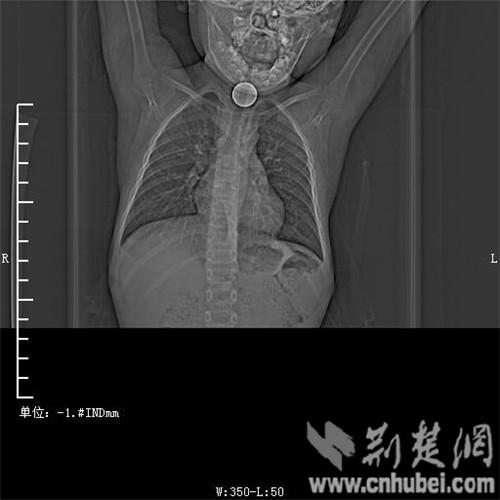

圖為:硬幣卡在了陽陽的喉部

消化內(nèi)主任方向明告訴記者,孩子送來時已經(jīng)是晚上8點15分,醫(yī)護人員立即給孩子拍胸部CT確定硬幣的位置,8點30分,方向明通過胃鏡下食管異物取出術(shù),成功的將這枚一元硬幣取了出來。1月5日上午,陽陽順利出院,醫(yī)生護士在他出院時不斷告訴他,以后千萬不要吞含異物。